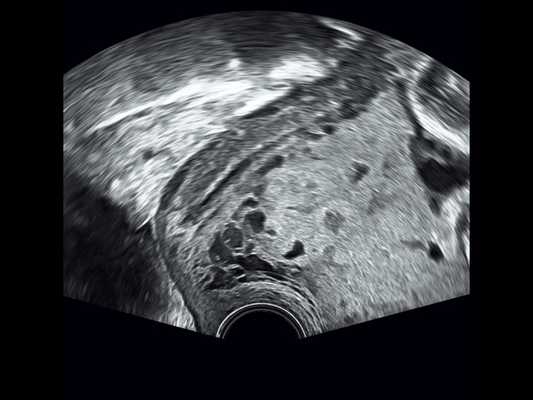

В 28 +6 нед беременности (рис. 1-3) при трансвагинальном сканировании выявлено прорастание плаценты в верхнюю треть шейки матки и цервикальный канал (PAS 3a).

Рис. 2. Беременность 28 +6 нед. Ретроплацентарные лакуны в шейке матки. Режим 2D.

Сканирование в сроке 32 +4 нед беременности проводилось на ультразвуковом сканере премиум-класса W10 (компании Samsung) c использованием конвексного (CA1-7A) и внутриполостного (EV3-10B) датчиков с применением технологии LumiFlow™ (рис. 4-7).

Рис. 6. Беременность 32 +4 нед. Трансвагинальное сканирование: ретроплацентарные лакуны в шейке матки и цервикальном канале.

В режиме серошкального сканирования все ранее идентифицированные особенности плацентации (PAS 3a): ретроплацентарные лакуны, васкулярная инвазия в шейку матки, исчезновение нормальной гипоэхогенной ретроплацентарной зоны, истончение миометрия, выпячивание плаценты, гиперваскуляризация пузырно-маточной зоны были подтверждены.

Дополнительное использование технологии стереоскопической визуализации кровотока (LumiFlow™) позволило визуализировать вовлеченность стенки мочевого пузыря беременной в конгломерат тканей аномальной плацентации (сосудистые мостики (rail sign) из миометрия сквозь серозный покров в стенку мочевого пузыря), то есть идентифицировать placenta percreta (PAS 3b). Проведенная в последующем МРТ констатировала полное предлежание плаценты с прорастанием в рубец, через все слои миометрия, шейку матки и цервикальный канал (рис. 8) и верхнюю стенку мочевого пузыря.